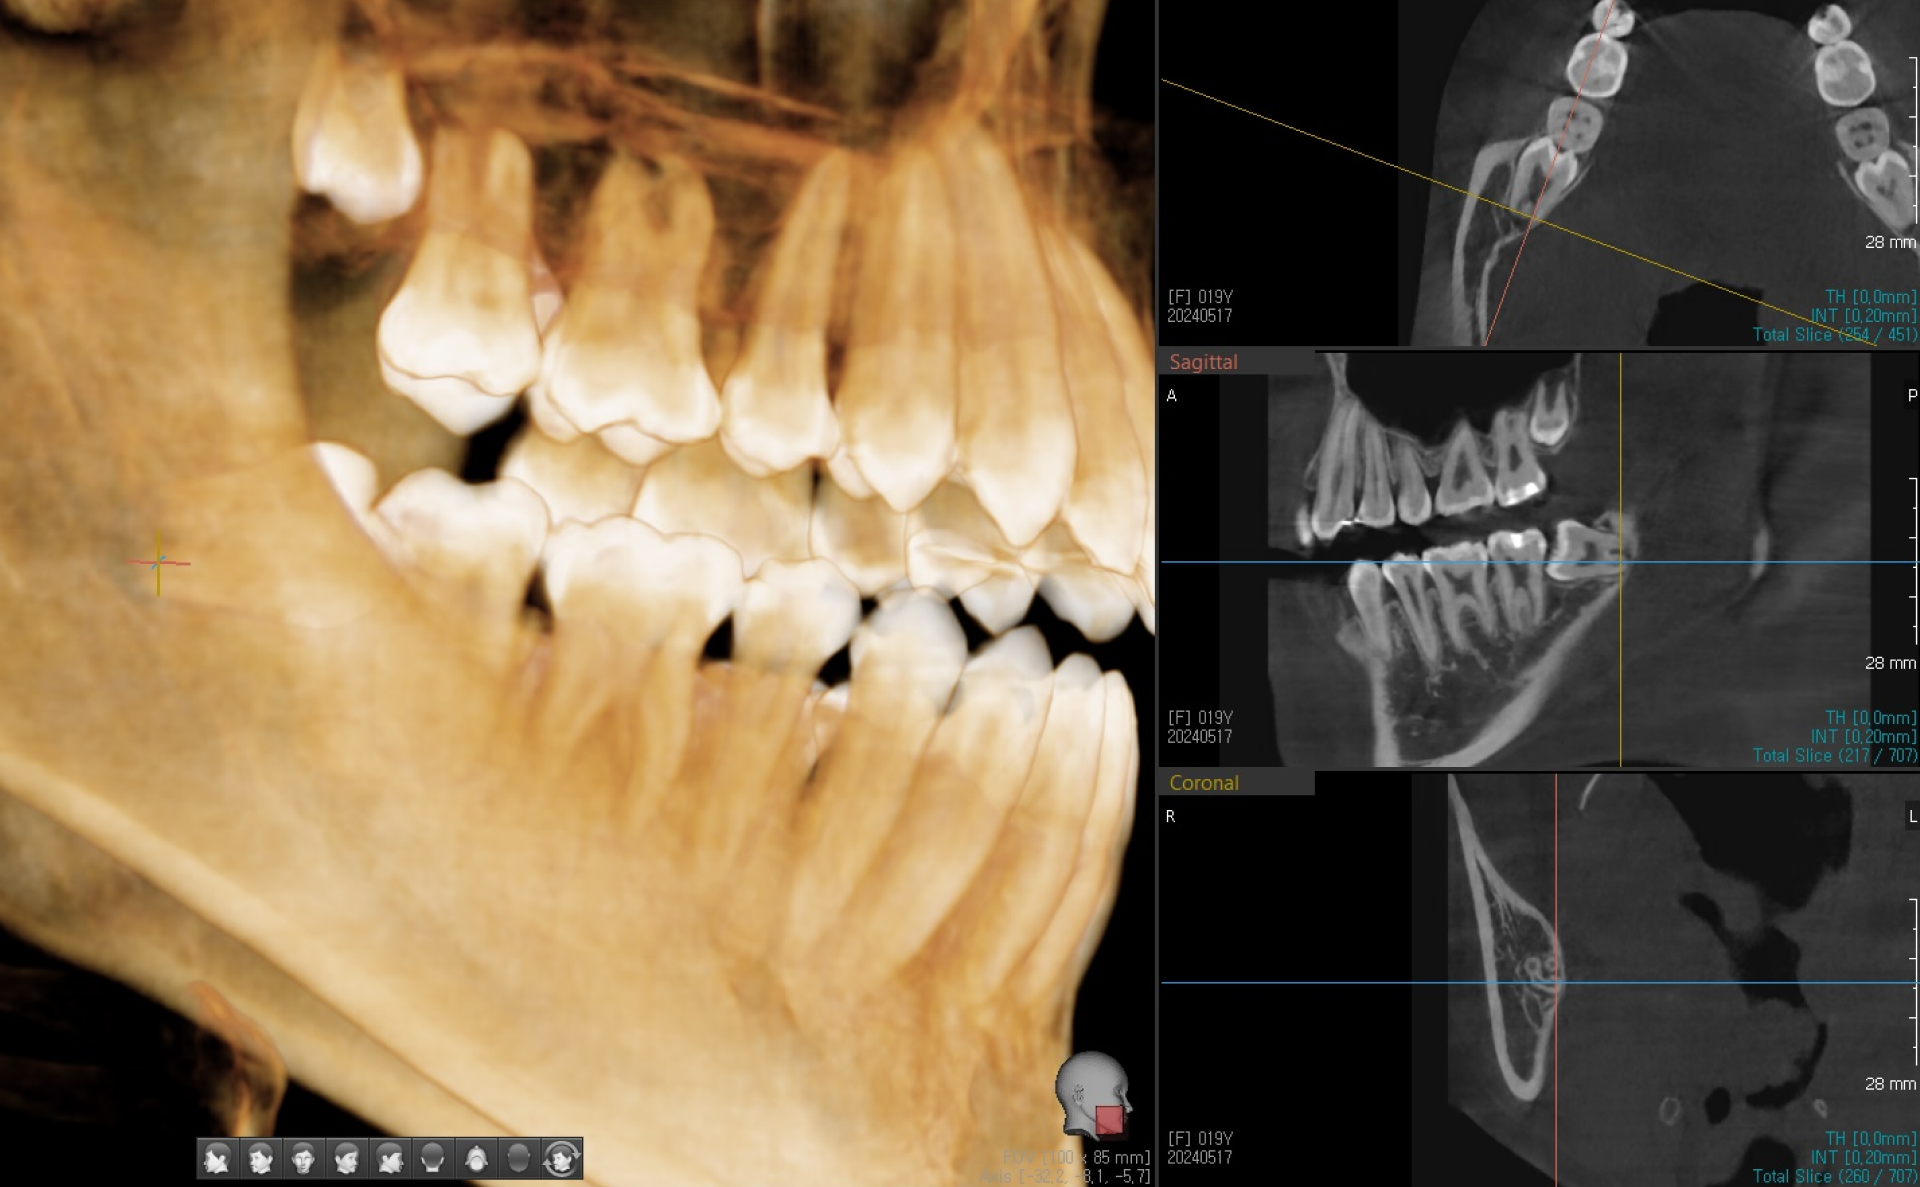

CT를 통한 3차원 영상이 있어야, 신경관과 사랑니의 위치 관계 및 거리를

정확하게 확인할 수 있고, 이를 바탕으로 발치를 진행해야

신경 손상 가능성을 최소화할 수 있습니다.